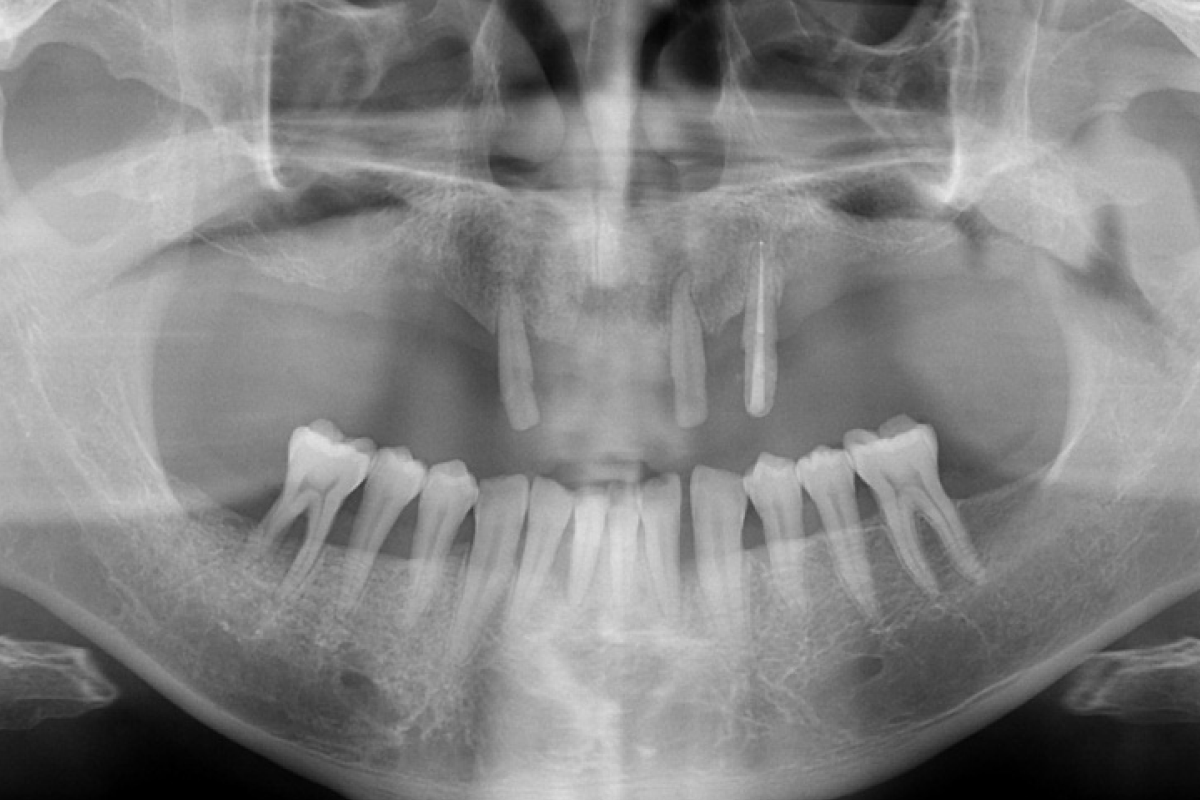

임플란트 치료 전 X-ray

BEFORE AFTER

실제 진료에서는 환자 개개인의 골 상태, 잇몸 상태, 전신질환 여부를 종합적으로 평가하여 임플란트 전·후를 예측하고 계획한 뒤 치료를 진행합니다.